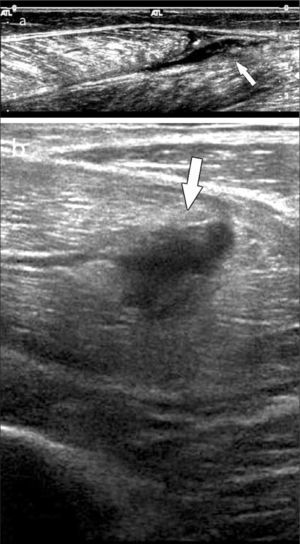

El tendón de Aquiles por sus características anatómicas y función particulares, a veces genera un examen ecográfico propio. Puede manifestar patología de distintas maneras, además de la tendinopatía similar a los otros tendones, incluso cálcica, en el tendón de Aquiles se puede encontrar engrosamiento del peritendón (no tiene vaina sinovial), aumento de vascularización, bursitis periaquilianas, alteraciones en la grasa de Kager, roturas parciales intrasustancia o completas en tercio medio o en la unión miotendínea con el tríceps sural (figura 11) (28).